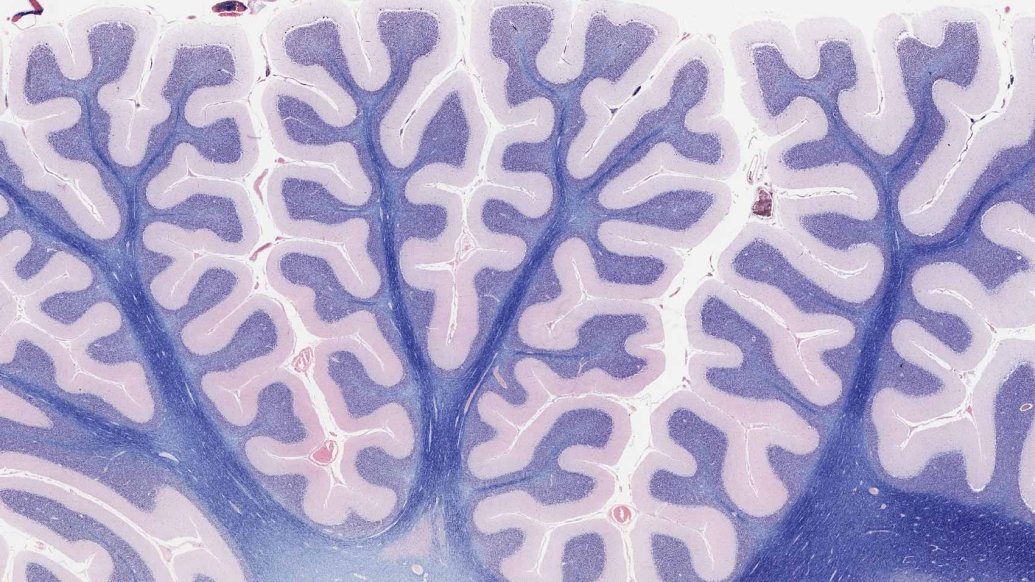

Top photo: A view of the "folds" of the brain's second-largest region, the cerebellum. Using virtual microscopy, educators and students can zoom into any region of such images, going from an organ-level to a tissue-level to a cell-level view.

(Images credited to: Michigan Histology and Virtual Microscopy Learning Resources)